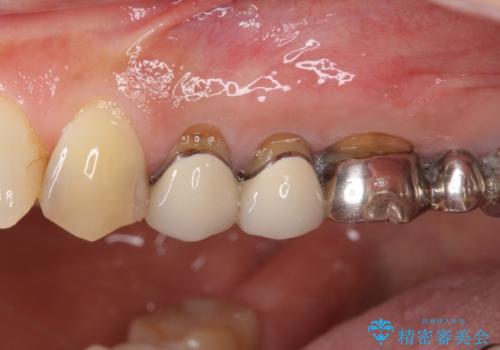

- 歯肉が退縮したためにクラウンの縁や歯根が見えてしまっていることを気にして来院された患者様です。

仮歯に変えた後にオールセラミッククラウンにて補綴することとしました。

強い咬合力や磨きすぎなどにより、歯根が見えてしまったり、金属の縁が見えてしまったりし、審美障害を引き起こすことがあります。

歯根が変色してしまうと、歯肉越しに歯根の黒い色が透けてしまうことがあり、この点についてはどうにも施しようがないため、患者様には事前のご理解いただきました。